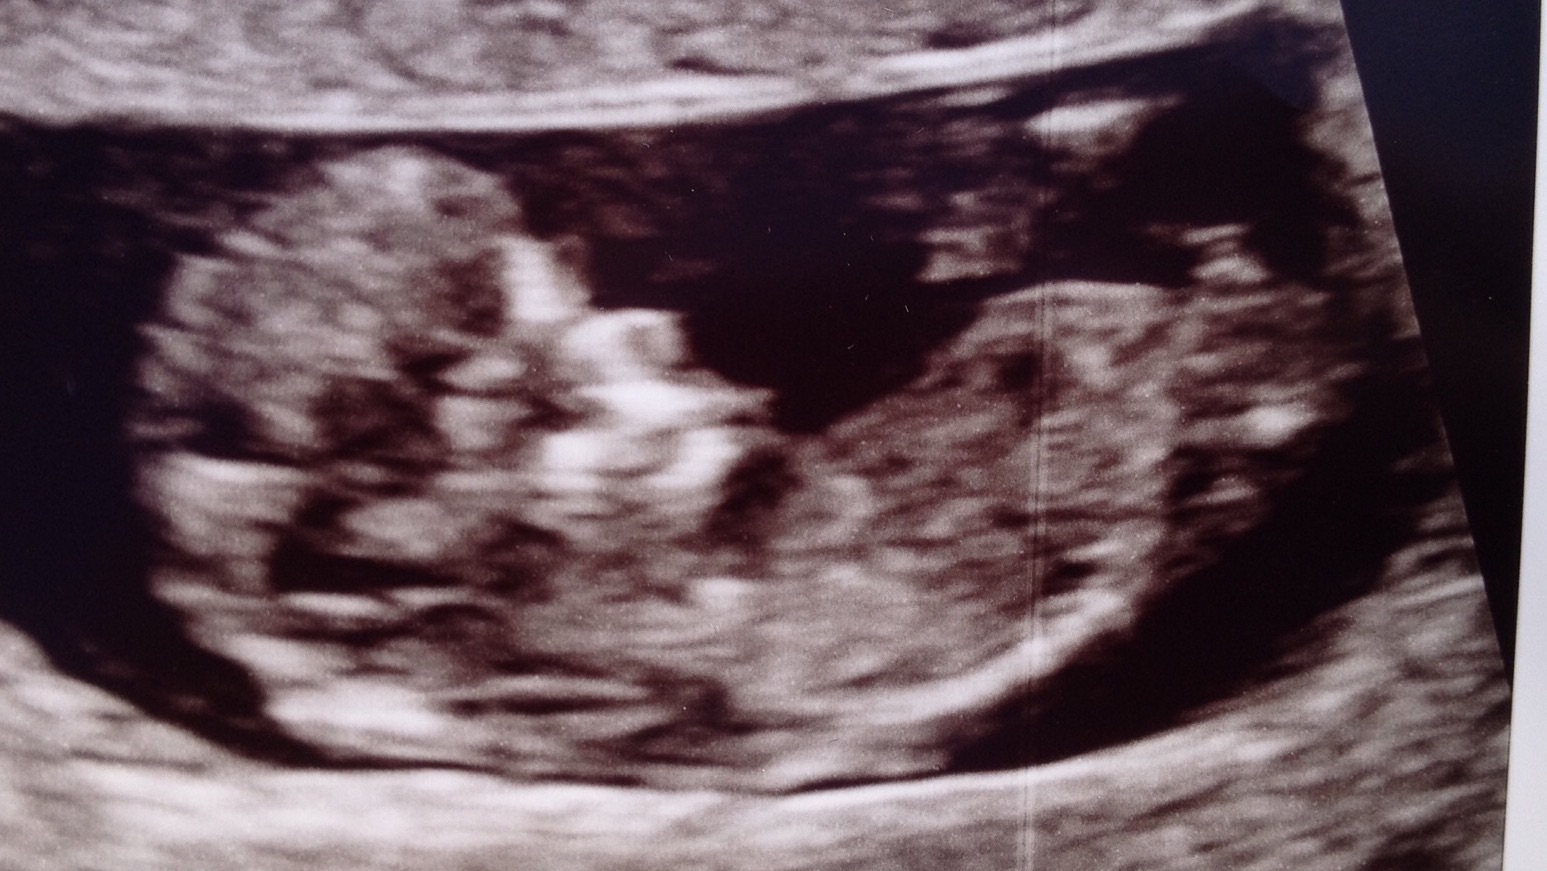

I'd really love some help. This is a pic taken at 11w3d. From what I can see snd others have pointed out it has a VERY clear stacked nub. Three lines stacking up towards the right of the pic. Am I going mad on thinking this is really early to be seeing stacking OR do I have a very definite boy in there?

Any clarification or thoughts would be really appreciated! I get that it's early but....that's boy stacking isn't it?! Or....does 3 lines mean girl??